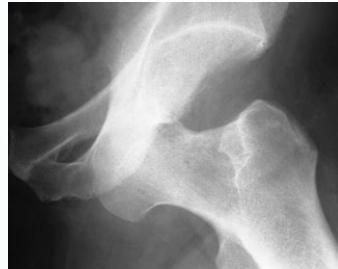

Posterior Hip Dislocation

Clinical Picture:

- Pain, Inability to move hip

- On examination: Limb is short, adducted, internally rotated & slightly flexed

Imaging:

- X-ray & CT scan

- R/O an acetabular fracture (or intraarticular bony fragment)